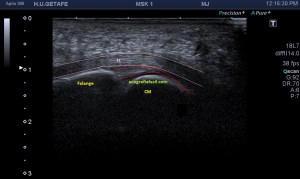

Al explorar la parte interna del muslo, en la zona donde nos señala la paciente encontramos esto…

Rotura

Una imagen de semiología heterogénea que me pareció una rotura fibrilar importante afectando al interior de un músculo de localización interna del que en un primer momento sospeché que podía ser el vasto interno, pero la anatomía no cuadraba, demasiado interno, demasiado cerca de los vasos…

Después de estudiar la rotura en dos planos (imagen 1 y 2) y medirla (imagen 3 y 4), documentarla bien referenciándola con la anatomía locorregional, incluidos los vasos (imagen 5), decidí seguir el recorrido del músculo partiendo desde la rotura siguiendo las instrucciones que me había comentado la paciente y me dí cuenta que el músculo afectado cruzaba el muslo desde el tercio proximal del muslo, en la cara anterior de la cadera (en su porción más superficial) hasta la cara interna de la pierna…en concreto desde la espina iliaca antero superior y terminando en la inserción de la Pata de Ganso.

En la imagen 1 observamos la rotura en eje corto, mas flechas rojas señalan el músculo dañado, las amarillas la rotura en si. Observamos la anatomía que la rodea y que es referencia siempre.